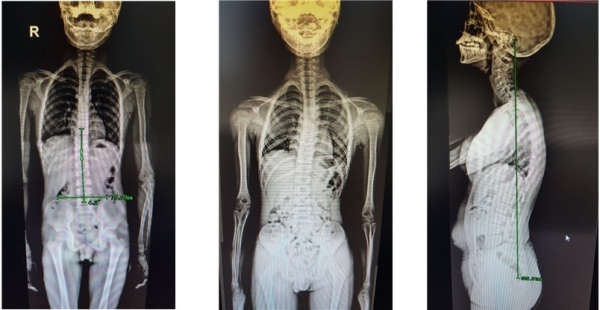

- 학생들의 건강상태의 변화가 파악되면 학교는 코로나 극복 정책의 하나로 체육 수업을 강화하여 측만증을 극복하거나 식단의 변화 등을 통해 비만해소를 위한 노력을 할 수 있습니다.

▲ saenal2

▲ 학생 건강검진 결과 나타난 비만 및 그와 연관된 척추측만증(출처 : 송파 파인의원)